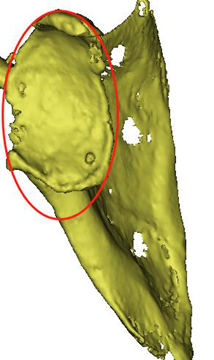

当地医院建议转上级医院治疗,患者以“夏科氏肩关节病”收住科室。患者存在脊髓空洞症,右肩受累关节端硬化更明显,伴骨质增生、破坏、骨膜反应、关节脱位、关节面破坏、塌陷,关节脱位,关节周围软组织肿胀,软组织内不规则钙化斑或碎骨片。关节周围肩袖松弛缺失。

术前X线,肱骨头,肩关节盂缺损严重